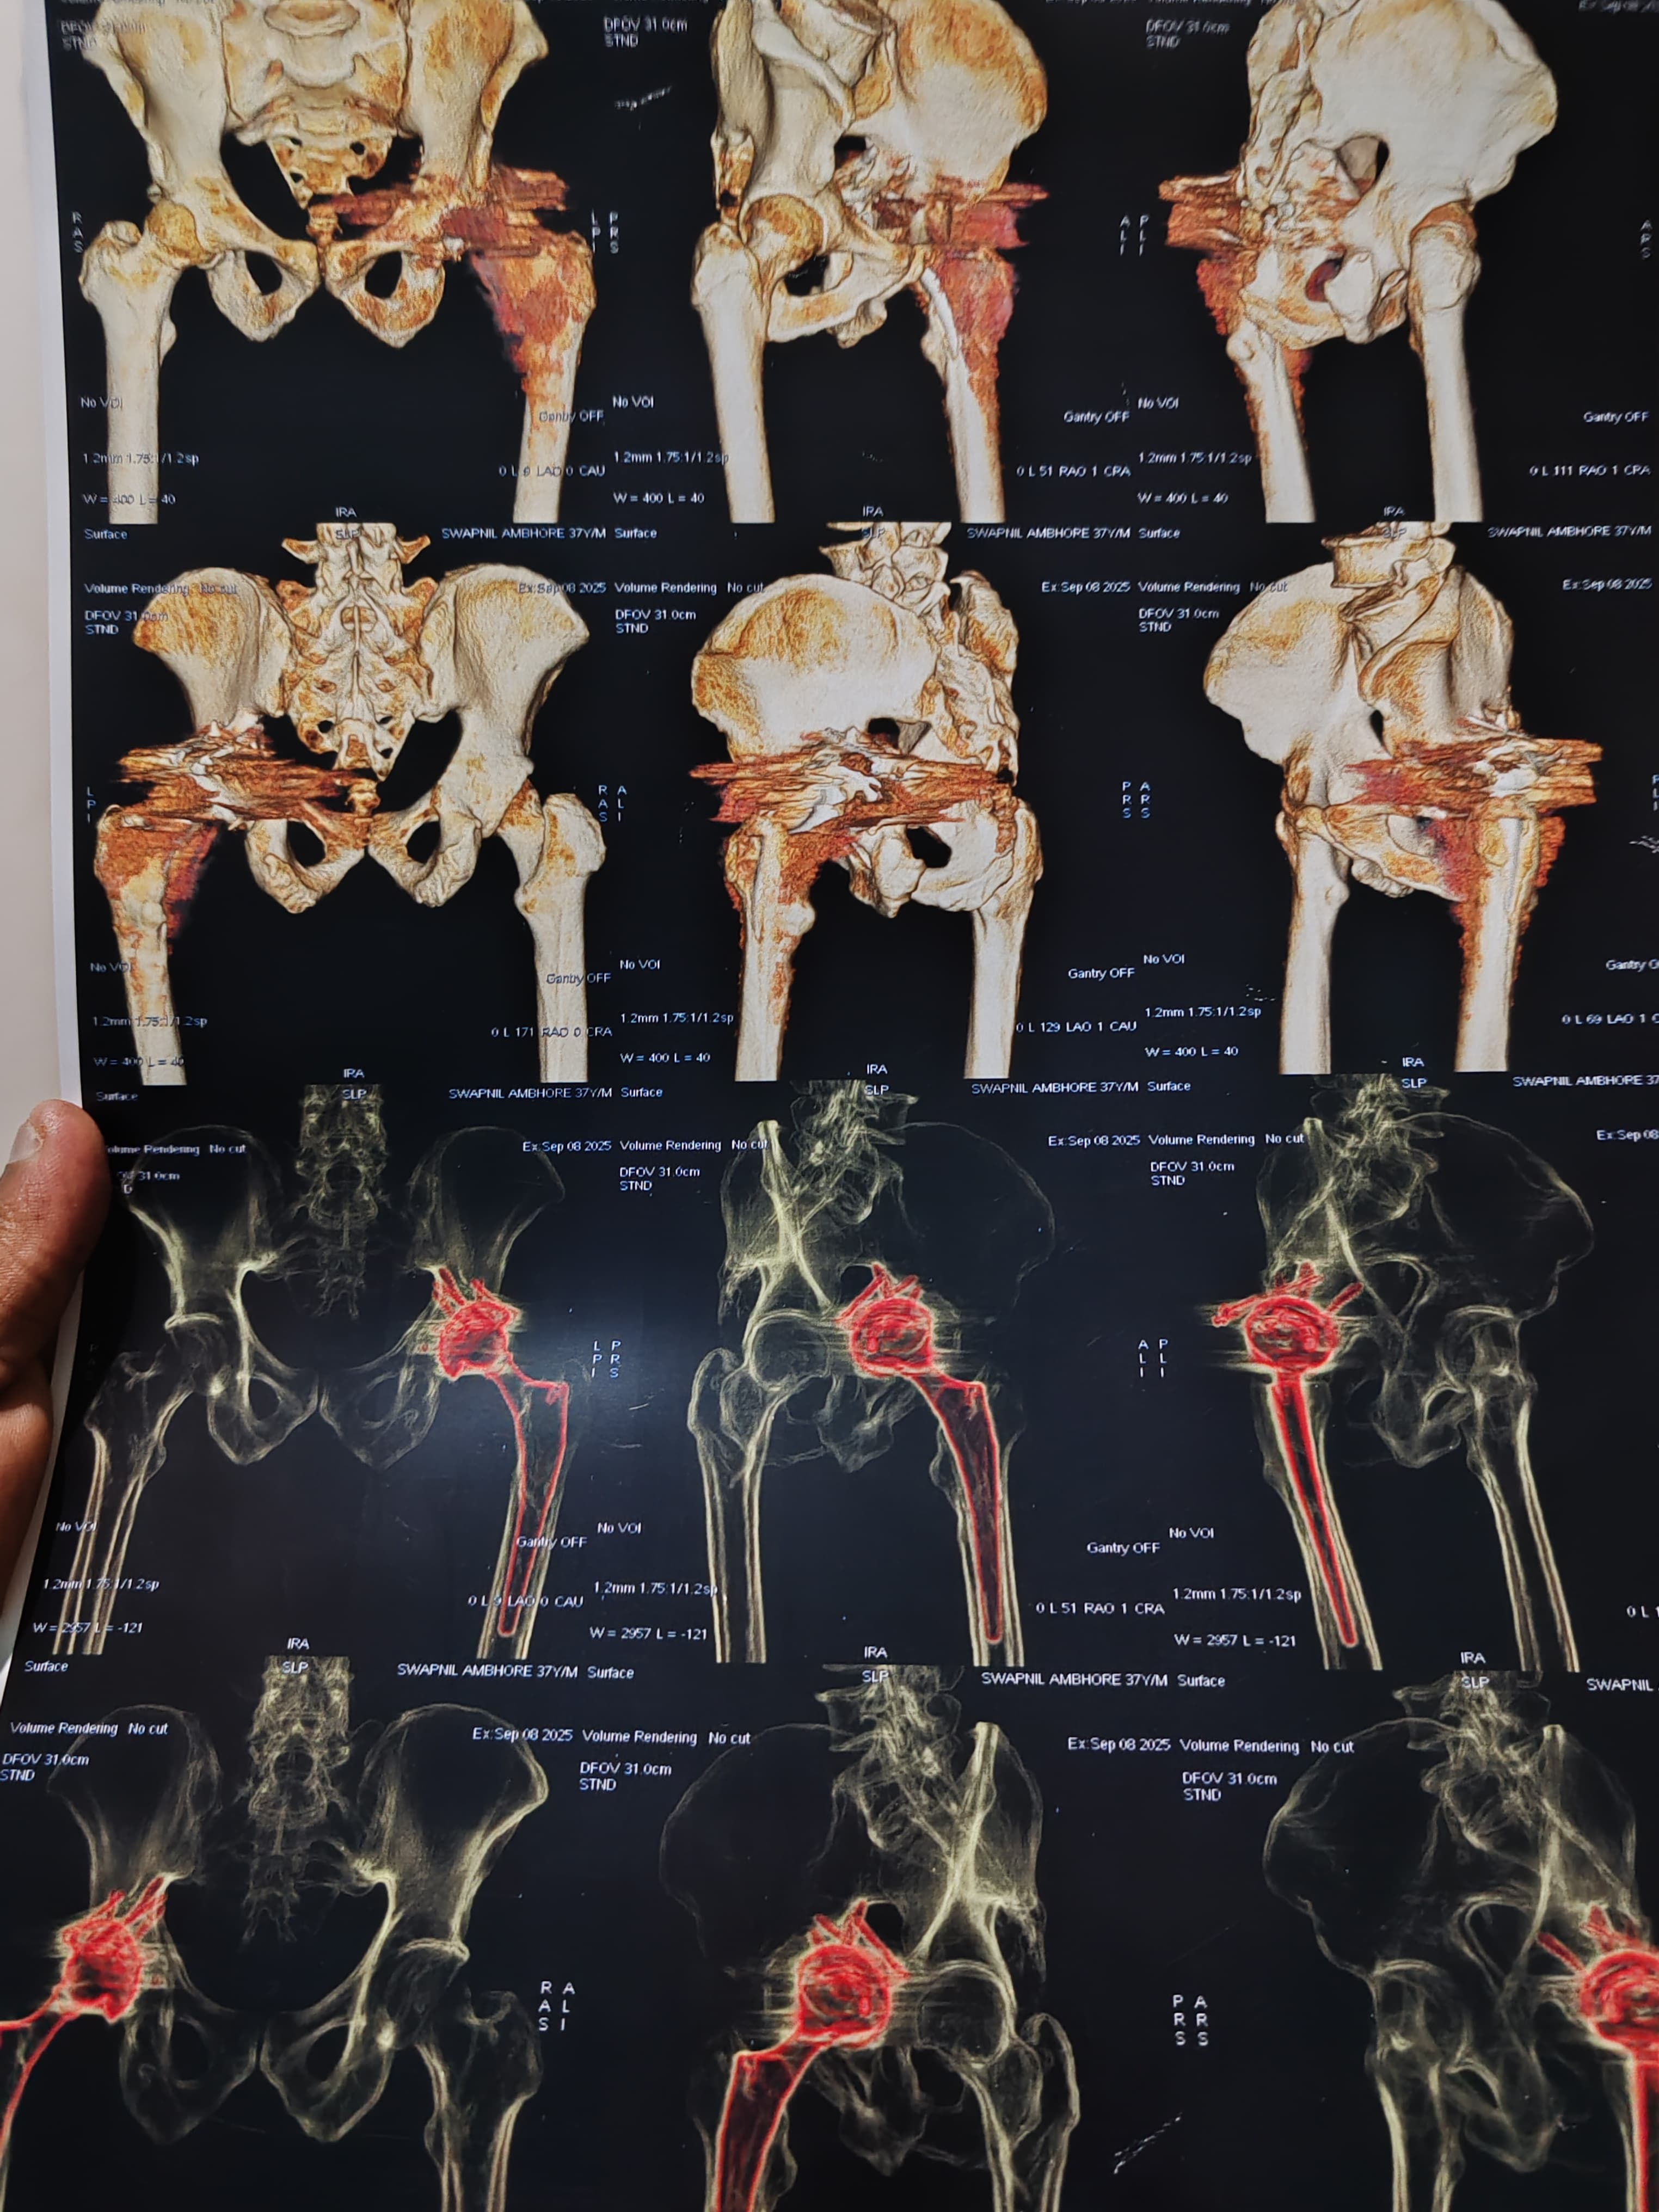

Dr Ajay Randive : IS MS Ortho (Mumbai) MRCSI ( UK) Consultant knee, Hip ,& Spine Surgeon, Dr Ajay Randhive is a eminent Knee, Hip , & Spine Surgeon practicing in to areas Andheri East,Santacruz East. Dr Ajay Randive did his MS Ortho residency from LTMMC, Sion Hospital Mumbai. He did overseas training in UK from 2003 till 2008. He is trained in total Knee Replacement, Hip Replacement, Revision Hip Replacement And Revision Knee Replacement Surgeries. He has worked at The Royal London Hospital. IN London where he worked a clinical fellow in joint Replacement unit. He has carried out more than 5000 Knee Replacement surgeries, 2500 Hip Replacement Surgeries, More Than 500 Revison Knee And Hip Replacement Surgeries 600 Spine surgeries & more than 1500 arthroscopic surgeries (Knee & Shoulder).